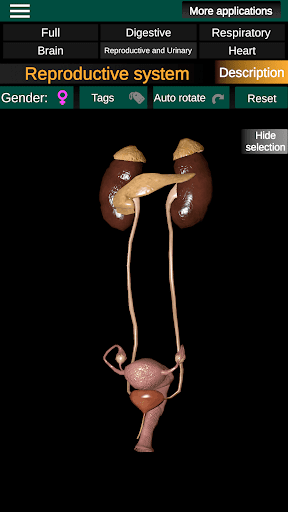

* Voortplantingssysteem, dat de mannelijke en vrouwelijke voortplantingsorganen omvat.

* Vergelijk mannelijke en vrouwelijke organen.

* Beschrijvingen van elk orgel.